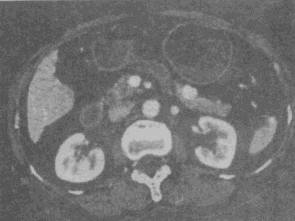

根据所提供的图像,最可能的诊断是<img border="0" style="width: 300px; height: 224px;" src=&quo

-

[单选题]根据所提供的图像,最可能的诊断是A.胰腺癌B.胰岛细胞瘤C.胰腺炎D.胰腺囊腺癌E.血管瘤

- 查看答案